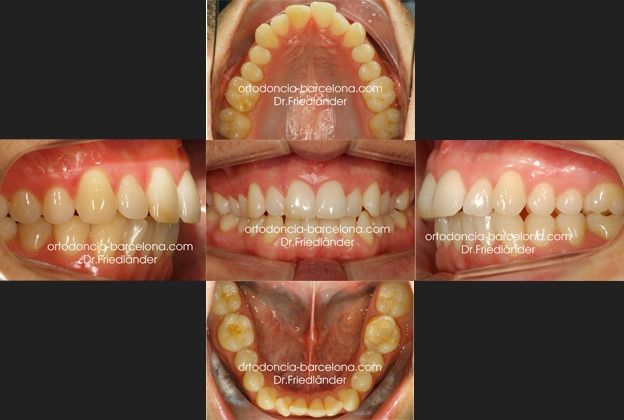

Fotos de antes del tratamiento

El siguiente tratamiento con Invisalign Full es de un paciente de 34 años que acude a nuestra consulta por motivos estéticos. Ya en la primera visita se observó la clase II (mandíbula retruída) y desviada hacía la izquierda; y una tendencia a la mordida abierta por deglución atípica. (la lengua empuja los dientes en lugar de subir al paladar a la hora de tragar).